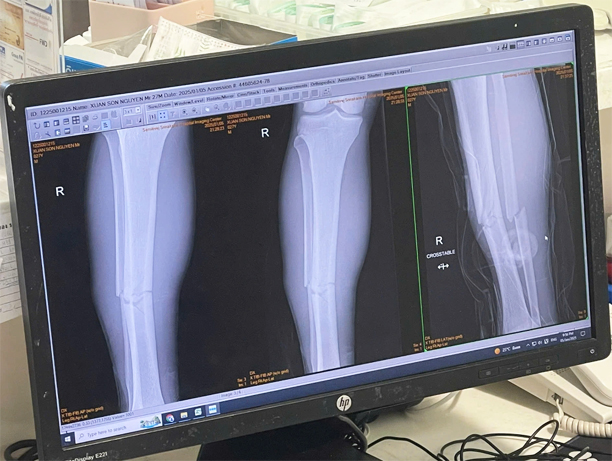

Theo kết quả chụp chiếu tại bệnh viện, Xuân Son đã bị gãy 2 xương ở ống chân phải, cần nhiều thời gian để điều trị và hồi phục. Hiện chưa rõ thời điểm tiền đạo số 12 của ĐT Việt Nam có thể tái xuất.

Kết quả chụp ống chân phải của Xuân Son